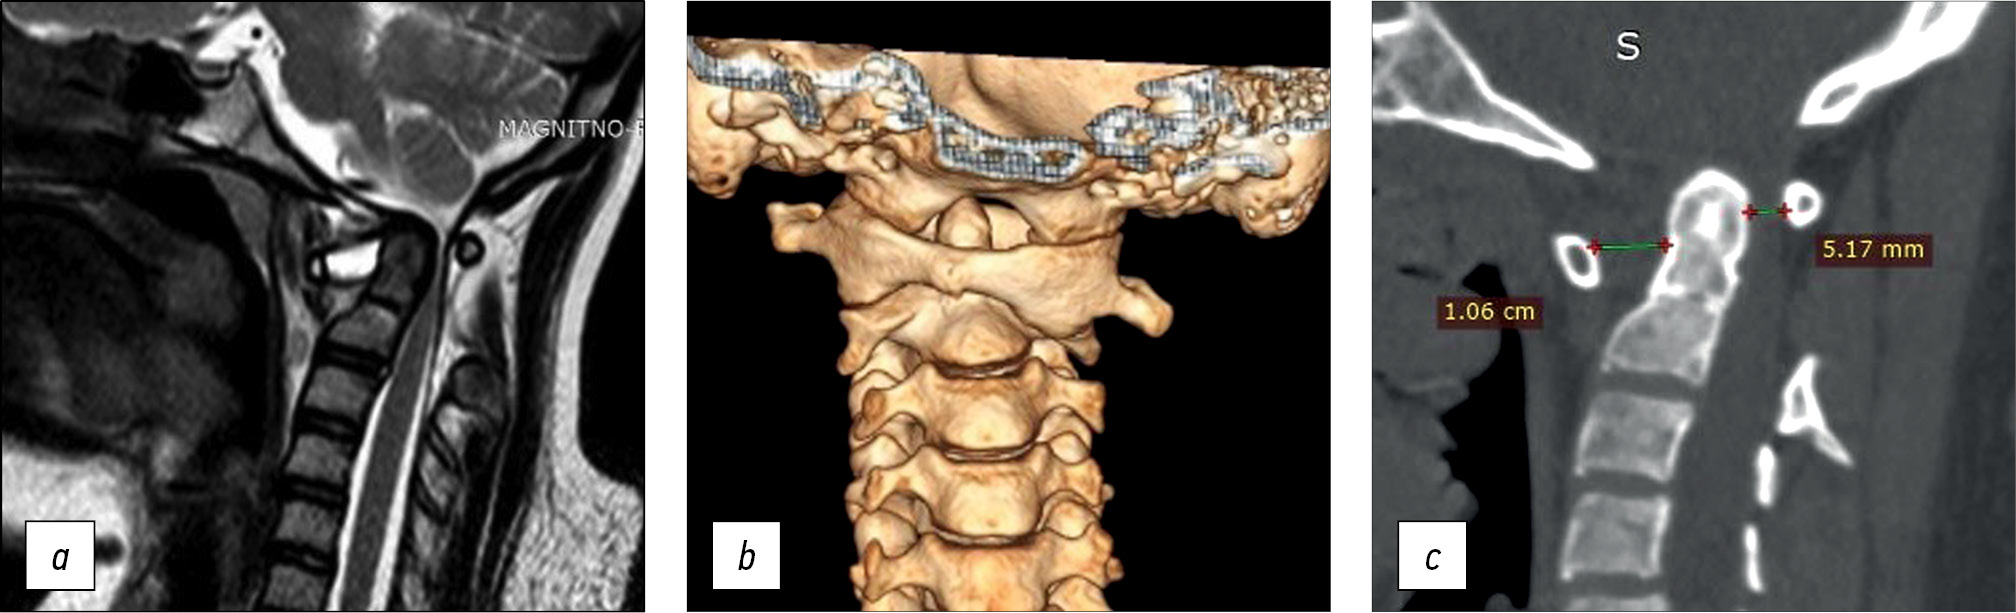

A 14-year-old female teen was admitted for a cervical spine screening examination in individuals with Down syndrome. She complained of progressive weakness in the upper and lower extremities and forced head position with rotation to the right for the past 3 months. Results of the CT and MRI of the cervical spine led to the following diagnosis: Down syndrome, rotational atlantoaxial blockage, left-sided chronic transligamentous subluxation of the C1 vertebra with spinal canal stenosis (Fielding–Hawkins type II), cervical myelopathy, and deep tetraparesis (Frankel C) (Fig. 2).

Fig. 2. Instrumental methods of examination: a — MRI picture of transligamentous subluxation with spinal canal stenosis and myelopathy at the level of C1-C2, b — 3D CT reconstruction, c — CT scan of the cervical spine, sagittal slice with visualization of disturbed craniovertebral relations. MRI — magnetic resonance imaging, CT — computed tomography.

CT revealed gross violations of craniovertebral relationships: the Cruveilhier joint gap (atlantodental interval [ADI]) was 1.06 cm, and the space available for the spinal cord at the C1 level (SAC C1) was 5.17 mm. These changes indicate gross stenosis of the spinal canal. A bone block developed in the left lateral atlantoaxial joint (Fig. 3)